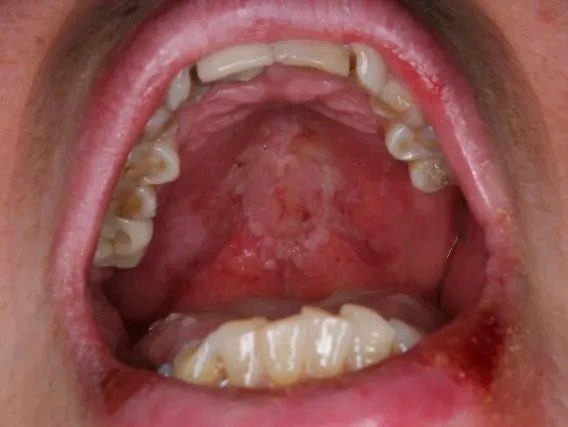

可致口腔黏膜形成血疱,血疱破溃后可形成口腔糜烂。进食火锅类食物引起软腭不规则糜烂面